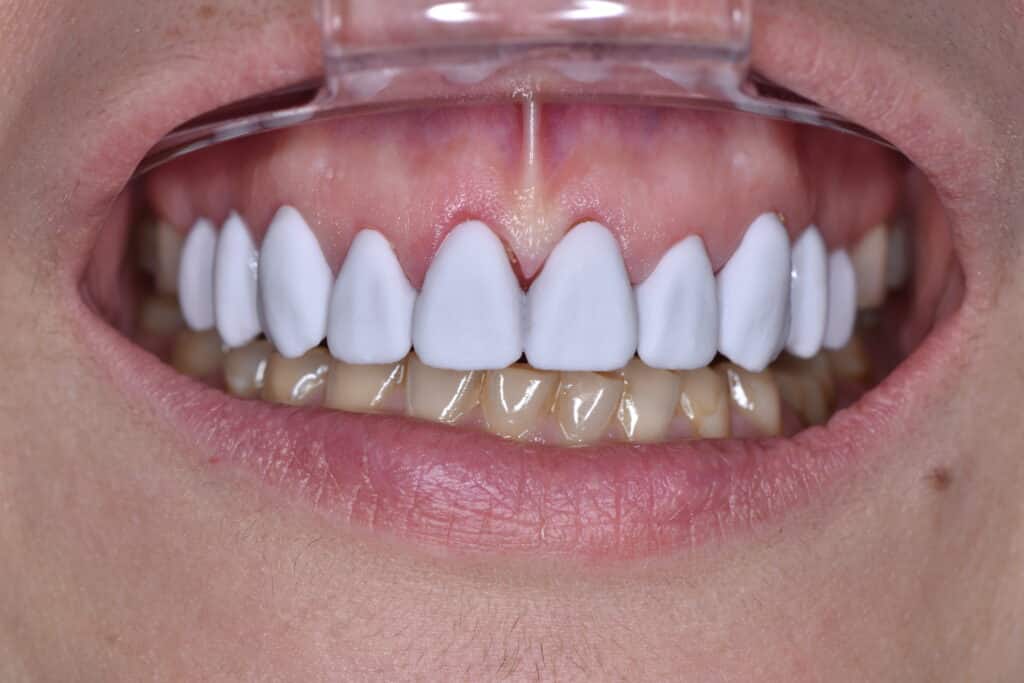

Der am Monitor visualisierte Vorschlag der verlängerten Zahnkronen mit provisorischen Restaurationen wurde mit der Patientin in der Praxis in Anwesenheit des Autors besprochen (Abb. 4 und 5).

Mit dem realen Bild der Patientin und einem biometrischen Smile Design, das ihren Gesichtsproportionen entsprach und die ursprüngliche Zahnkronenlänge be-rücksichtigte, war die Patientin schnell überzeugt.

Zusätzlich erhielt die Patientin einen Link, damit sie das Smile Design auch auf ihrem Smartphone sehen und im Freundes- und Familienkreis besprechen konnte. Auf diese Weise konnten Zahnarzt und Zahntechniker ihr Vertrauen in den Behandlungsablauf stärken und die Simulation konnte zu einem verbesserten Verständnis für die Behandlungsop-tionen beitragen. Die Patientin willigte überzeugt in die Behandlung ein.